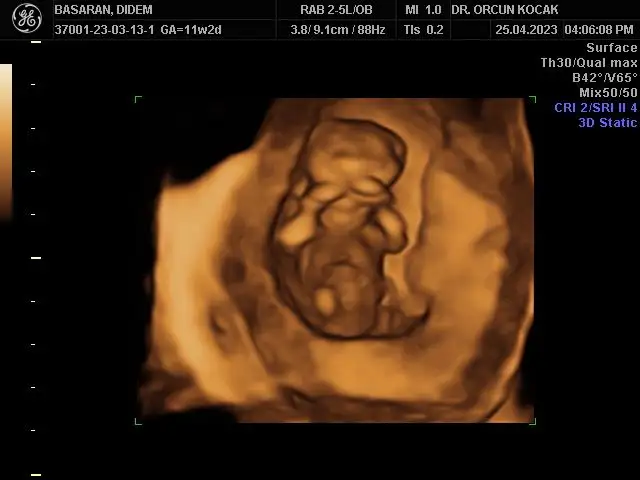

Merhabalar bende 11+5 im tahminlerinizi çok merak ediyorum kızlar sizce ne olabilirRamzi de nub’ u da erkek görünüyor canım

Bu ultrason görüntüsü mü yoksa alttan mı? Ultrasonsa benimkiyle aynı da kafatası bile. Ay ultrason yazmışsın zaten ya farketmedim. Sağlıkla kucağına al inşallah evinize neşe getirsin.Ultrason görüntüsü bugünün böyleydiben erkek hissediyordum bu sefer bulantım filan olunca ama değilmiş hiç teorilere bakmadım açıkçası o yüzden bilmiyorum